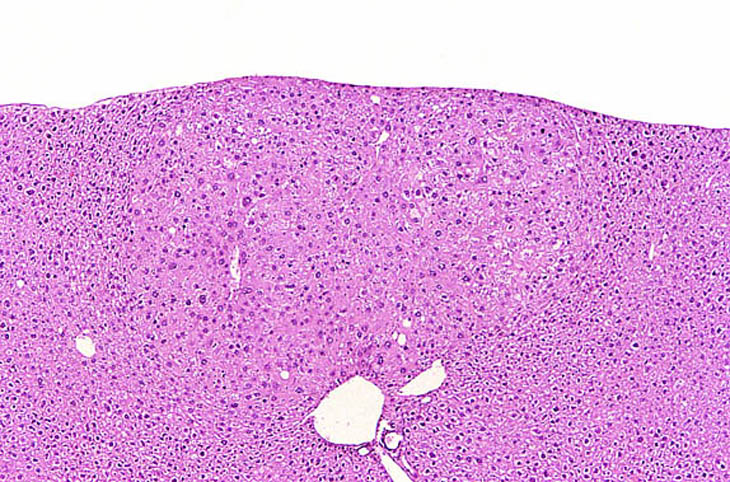

Hepatocellular adenomas are typically discrete proliferative lesions with loss of normal lobular architecture, absence of portal areas, and some degree of compression of adjacent normal hepatic parenchyma. The arrangement of the hepatocytes within an adenoma may be at right angles to the surrounding hepatic parenchyma. The tinctorial properties of hepatocytes within an adenoma may be basophilic, eosinophilic, pale, or mixed.

A large hepatocellular adenoma is present on the parietal surface of the left lobe.